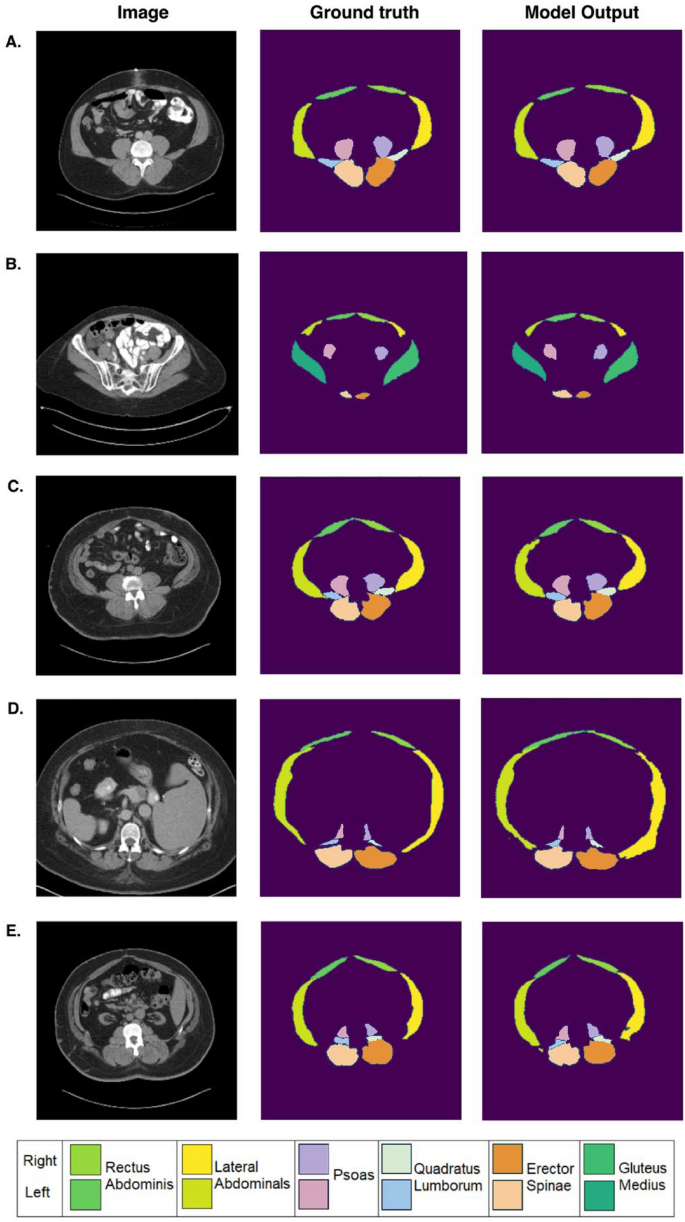

Examples of group-level abdominal muscle segmentation on axial abdominal CT scans in 5 representative patients. The first column shows axial abdominal CT images at different levels in patients. The second column shows ground truth labels, and the third column shows segmentations performed using machine learning. The corresponding Dice scores for each case are as follows: (A) Psoas: 0.969 (Left), 0.963 (Right); Quadratus Lumborum (QL): 0.922 (Left), 0.946 (Right); Erector Spinae (ES): 0.950 (Left), 0.946 (Right); Gluteus Medius (GM): N/A; Rectus abdominis (RA): 0.853 (Left), 0.868 (Right); Lateral abdominals (LA): 0.960 (Left), 0.947 (Right). (B) Psoas: 0.883 (Left), 0.864 (Right); QL: N/A; ES: 0.842 (Left), 0.782 (Right); GM: 0.912 (Left), 0.910 (Right); RA: 0.904 (Left), 0.898 (Right); LA: 0.740 (Left), 0.764 (Right). (C) Psoas: 0.915 (Left), 0.901 (Right); QL: 0.942 (Left), 0.912 (Right); ES: 0.968 (Left), 0.935 (Right); GM: N/A; RA: 0.890 (Left), 0.906 (Right); LA: 0.893 (Left), 0.916 (Right). (D) Psoas: 0.922 (Left), 0.904 (Right); QL: 0.887 (Left), 0.847 (Right), ES: 0.964 (Left), 0.952 (Right); GM: N/A; RA: 0.894 (Left), 0.907 (Right); LA: 0.911 (Left), 0.876 (Right). (E) Psoas: 0.871 (Left), 0.742 (Right); QL: 0.881 (Left), 0.772 (Right); ES: 0.930 (Left), 0.941 (Right); GM: N/A; RA: 0.834 (Left), 0.896 (Right); LA: 0.848 (Left), 0.886 (Right).